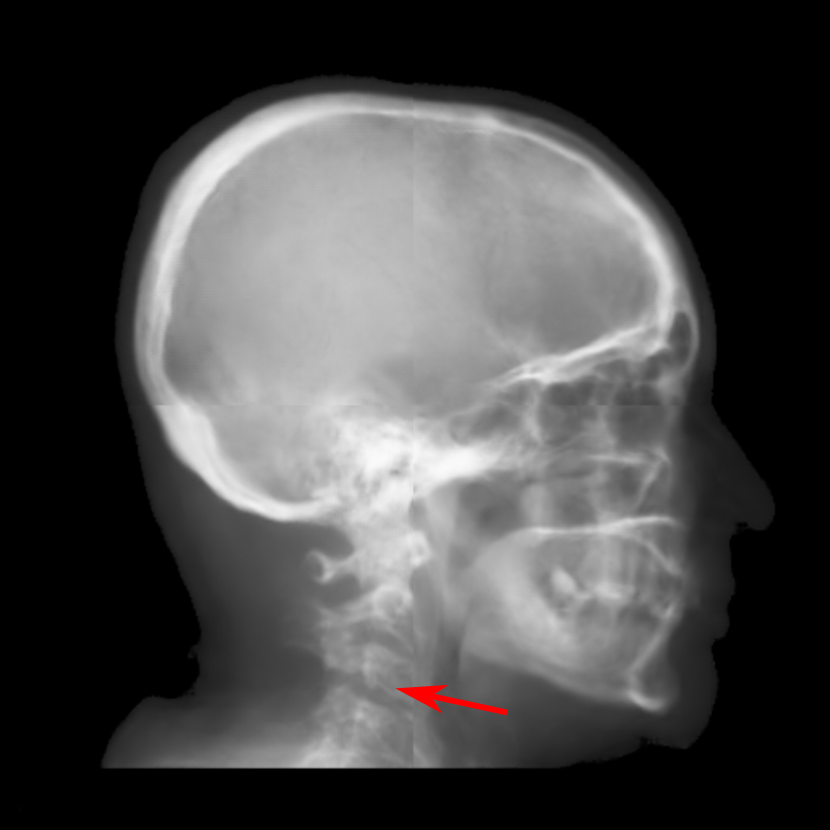

Fig. 16: Landmark detection on synthetic cephalograms. Cephalograms in the top row are obtained by different synthesis methods from 3D volumes for the first patient with pix2pixGAN for SR. The second row shows Type I synthetic cephalograms with different SR methods. The 3rd and bottom rows are Type I and Type II synthetic cephalograms respectively from three example patients with pix2pixGAN for SR. The green (reference) and blue labels are manual detection landmark positions in Type I and Type II synthetic cephalograms respectively, while the red labels are automated detection landmark positions in each cephalogram.

Our proposed landmark detection method is applied to detect landmarks in synthetic cephalograms. The results of three example patients are displayed in Fig. 16. Cephalograms in the top row are obtained by different synthesis methods from 3D volumes for the first patient with pix2pixGAN for SR. The second row shows Type I synthetic cephalograms with different SR methods. The 3rd and bottom rows are Type I and Type II synthetic cephalograms respectively from three example patients with pix2pixGAN for SR. The green and blue labels are manual detection landmark positions in Type I and Type II synthetic cephalograms respectively, while the red labels are automated detection landmark positions in each cephalogram. The green labels are used as the reference. The overall SDRs of the landmarks in different types of synthetic cephalograms on the test patients are displayed in Tab. 4. The last row SDRs are calculated from manual detection (blue) landmarks in Type II synthetic cephalograms w. r. t. reference landmarks, while others are from automatic detection (red) landmarks w. r. t. reference landmarks.

For RayCast in Fig. 16(a), many automatic detection landmarks exceed the 4 mm precision range such as the landmarks of anterior nasal spine, gonion, porion and articulare. According to Tab. 4, overall only 45.6% landmarks are detected within the 4 mm precision range by the automatic landmark detection algorithm. For MIP100 in Fig. 16(b), the landmarks of sella, porion, articulare have very large deviations from the reference landmarks. Overall, it achieves 47.4% 2 mm-SDR and 81.5% 4 mm-SDR. Figs. 16(c) and (g) are the cephalograms synthesized by our Type I synthesis with the original sigmoid transform and the modified sigmoid transform, respectively. These two synthetic cephalograms have subtle difference in the soft-tissue areas. As a result, the detected incision superius and lower lip positions exceed the 4 mm range in Fig. 16(c) while they are well detected within the 2 mm precision range in Fig. 16(g). This demonstrates the benefit of the modified sigmoid transform.

In Figs. 16(d)-(f), the landmark detection accuracies are very close to each other for the other 18 landmarks except for the sella landmark. The point-to-point errors are 9.77 mm, 4.57 mm, and 1.65 mm respectively in Figs. 16(d)-(f) for the sella. Tab. 4 indicates that overall 66.7% landmarks are detected within the 2 mm precision range for bicubic interpolation. For ESRGANRDB and ESRGANRRDB using ILR patches, the 2 mm-SDR rises to 70.2% and 71.9%, respectively. Nevertheless, pix2pixGAN achieves the best 2 mm-SDR 75.4% among different SR methods for Type I synthesis. Therefore, different SR methods have an influence on the landmark detection.

For Type I synthesis, two more cephalograms are displayed in Figs. 16(h) and (i). Overall, 93.0% automatic detection landmarks are overlapped with the reference landmarks within the precision range of 4 mm, with a few exceptions such as the sella landmark in (g), the porion in (h), and the incision inferius and subnasale landmarks in (i) beyond 4 mm. Particularly, 75.4% automatic detection landmarks are within the 2 mm clinical acceptable precision range. This indicates that the automatic landmark detection algorithms learned from real conventional cephalograms can be applied to our Type I synthetic cephalograms.

For Type II synthetic cephalograms in Figs. 16(j)-(l), all the manual detection (blue) landmarks are overlapped with the reference landmarks within the distance range of 4 mm, indicating that the landmark positions in the Type II synthetic cephalograms have no impactful position shift from those in Type I synthetic cephalograms. The majority (80.7%) of the automatic detection (red) landmarks are also overlapped with the reference landmarks within the 4 mm precision range. However, more automatic detection landmarks in Type II synthetic cephalograms are outside the 4 mm range than those in Type I synthetic cephalograms, for example, the anterior nasal spine landmark in (j), the orbitale landmark in (k), the incision inferius landmark in (l), the nasion landmarks in (k) and (l), and the gonion landmarks in (j)-(l). The 2 mm-SDR also decreases from 75.4% to 50.9%.